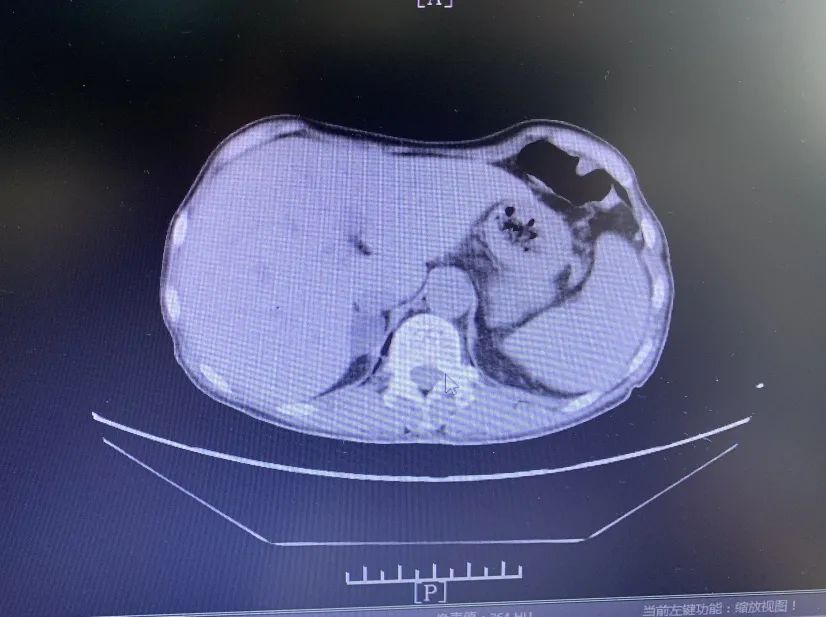

結(jié)合患者腹部CT及彩超的檢查結(jié)果,原來(lái),劉女士還患有右側(cè)輸尿管結(jié)石、左腎多發(fā)性結(jié)石,并且在腎上腺處還長(zhǎng)有一顆腫瘤。鄧超雄主任判斷,這些正是導(dǎo)致劉女士身體愈差的病根所在。